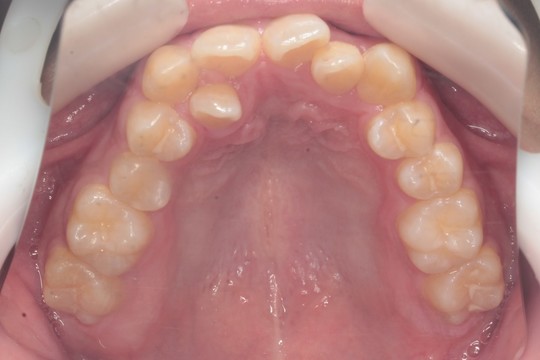

治療前

治療後

治療前後写真について

調布市の20代男性

主訴:歯並びをきれいにしたい

使用装置:インビザライン

治療期間:約3年

治療費用:93.5万円(税込)

治療結果:交叉咬合と叢生が改善されました